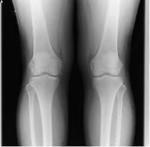

鵞足炎/膝の痛み

症例】鵞足炎/ひざの痛み

林璃子さん【17才】岐阜市・陸上

「3週間前から痛みが始まった」と訴えます。

昨年の冬にも膝を痛め、「今回が2度目です」

「前回と同じ場所ですが、今回の方が強いです」

走り込みと、筋トレで2か月間の疲労蓄積、練習後のメンテナンス不足が原因です。

背中から腰、腰から膝、足首までの筋肉硬化の強いアスリートでした。